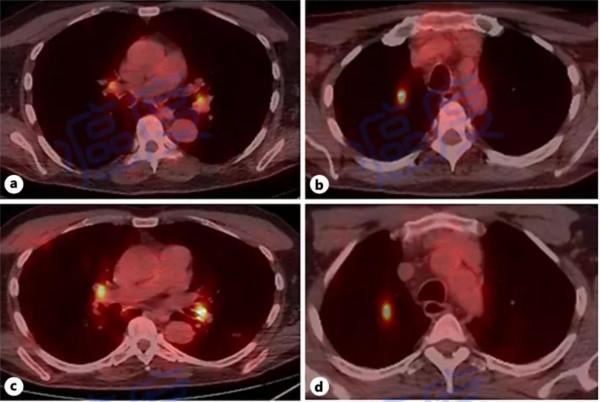

手術7周以後,進行的PET-CT掃描顯示有一個肺部結節,肺門淋巴結也有示蹤劑的吸收,患者出現了轉移。為此他接受了化療,並且對頸部進行了輔助放射治療。

接下來患者參加了臨床試驗裡的免疫治療研究,使用了4個週期的伊匹木單抗聯合納武利尤單抗,免疫治療導致了下肢水腫的不良反應,而病情並沒有得到控制,免疫治療4個月之後,進行的PET-CT檢查顯示病情進展。

患者瞭解到了之前的一些研究案例,嘗試使用沙利度胺,初期每天的劑量為150毫克,6周以後將劑量增加到每天200毫克。使用了沙利度胺一段時間之後,進行PET-CT掃描發現病情穩定。

在患者持續使用沙利度胺3個月之後,由於出現了周圍神經的不良反應(四肢水腫、行走問題),他將藥物劑量減到了每天50毫克,後面又改為每天使用10毫克來那度胺。在使用來那度胺16個月之後,患者的病情穩定,儘管PET-CT檢查顯示腫瘤細胞有代謝活性,但是自從使用沙利度胺之後,腫瘤沒有進一步生長。除去上面的神經病變之外,患者的體能良好。